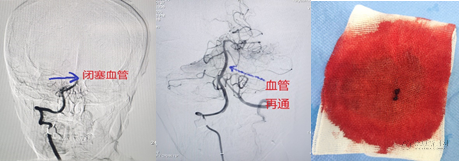

在杨国威主任的精准操作下,团队毅然迎难而上,成功施行“颅内动脉取栓术”,一次性成功取出致命血栓,实现了血管的完美再通。从入院到血管再通,全程仅用时90分钟,以最快的速度,为患者赢得了生机。